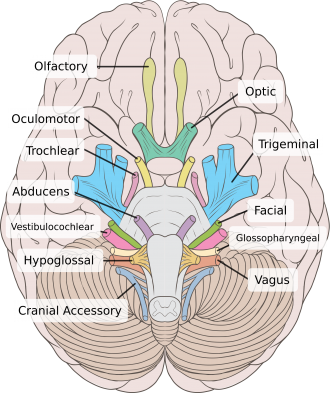

Info

感覺神經 1, 2, 8

運動神經 3, 4, 6, 11, 12

副交感 3, 7, 9, 10

| CN | Origin | foramen |

|---|---|---|

| I | 嗅球 | cribriform plate |

| II | Optic Chiasma | optic canal |

| III, IV | Midbrain | sup orbital fissure |

| V1, VI | pons | |

| V2 | foramen rotundum | |

| V3 | foramen ovale | |

| VII | Internal coustic meatus | |

| VIII | Pons, Medulla 之間 | |

| IX, X, XI | Medulla | jugular foramen |

| XII | Hypoglossal canal |